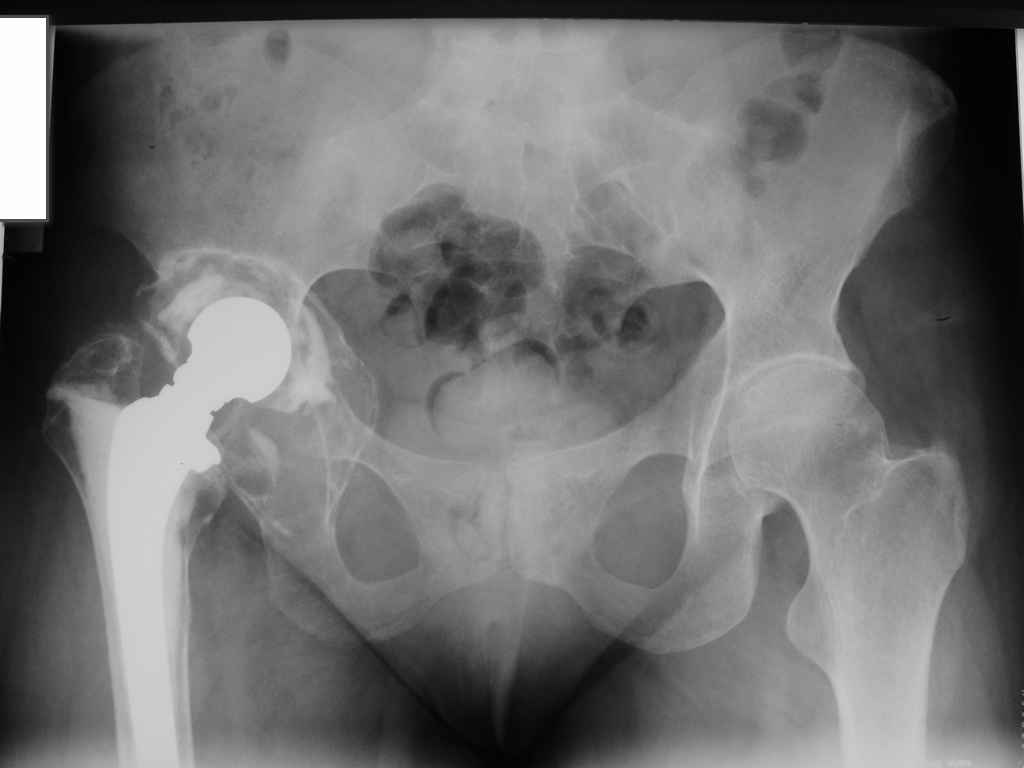

Больная 40 лет, поступила в отделение с диагнозом: Нестабильность чашки цементного эндопротеза Мовшовича правого тазобедренного сустава с протрузией тазового компонента.

Рентгенограммы от 07,07,2009г.

Данных за нестабильность ножки не выявлено. Помогите определиться с выбором оптимального варианта ревизии: